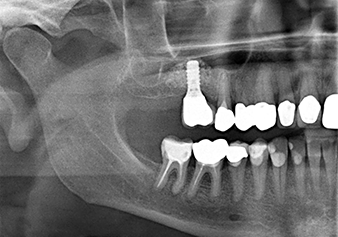

Une patiente de 49 ans, non fumeuse et sans antécédents médicaux remarquables, a été orientée vers notre cabinet de chirurgie orale pour l’extraction chirurgicale de la dent 16 préalable à la pose d’un implant. Après l’extraction, la patiente a rencontré de légers problèmes de sinusite, à la suite de quoi nous avons commencé par attendre six mois avant de prendre la mesure. À l’endroit prévu pour la pose de l’implant, l’os résiduel mesurait 3-4 mm de haut (Fig. 1 et 2).

Fig.2 : La DVT montre des dimensions adéquates sur chacune des vues axiale (gauche), latérale (dessus) et transversale (droite). La membrane du sinus maxillaire est encore légèrement épaissie.